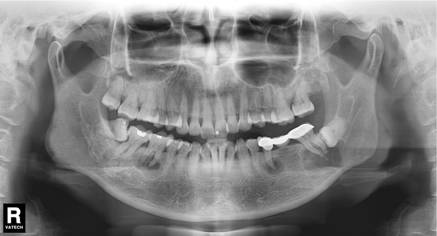

因此,如果牙齒出了問題,齒科醫(yī)生就需要有“透視”功能的X線片來檢查。通過x線片不僅能了解牙齒本身的病變情況,還可以了解牙根下有沒有囊腫、周圍骨頭有沒有吸收以及牙槽骨內(nèi)是否有埋伏牙、多生牙等。依據(jù)X線片綜合分析,可以提高齒科醫(yī)生診斷治療牙齒的準(zhǔn)確性和成功率。常見的牙科放射檢查包括曲面體層片( 全景片 )、小牙片、頭顱正側(cè)位片、全頭顱 CT、錐形束 CT( CBCT )等。由于牙齒下部隱藏在牙槽骨中,口腔醫(yī)生要了解牙齒的整體情況就需要拍攝全景片;要了解個別牙根及周圍變化,則選擇拍攝小牙片。醫(yī)生要判斷牙槽骨是否符合種植條件,或者了解埋伏阻生齒的三維位置以及其他頜骨內(nèi)病變組織的形態(tài)大小時,則需要進(jìn)一步拍攝 CBCT 。所以,拍牙片是一種幫助齒科醫(yī)生進(jìn)行診斷、治療、療效評估的重要手段,治療前用于發(fā)現(xiàn)病變程度、范圍;治療中用于引導(dǎo)治療、確定治療范圍和深度;治療后用于觀察療效。輻射分為電離輻射(如X光)和非電離輻射(如手機(jī)、微波爐),這里主要講述的是電離輻射。電離輻射的測量單位是西弗(Sv),但西弗是個非常大的單位,因此通常使用毫西弗(mSv)和微西弗(μSv),1Sv=1000mSv,1mSv=1000μSv)根據(jù)國際放射防護(hù)委員會(IRPA)提供的信息,每人每年受到的輻射劑量大約在2.5毫西弗左右,這個數(shù)值受地域緯度的影響而波動。其中大約80%來源于自然界,20%來源于人工輻射。而拍牙片是什么樣的輻射水平呢?根尖片為 5.2 μSv ,全口根尖片為 72.32 μSv ,曲面體層片為 10 ~ 23 μSv ,頭顱正位片為 1 ~ 5 μSv ,頭顱側(cè)位片為 1 ~ 3 μSv ,讓人「聞風(fēng)喪膽」的 CBCT 劑量一般也在 300 μSV 之內(nèi)。為了幫助大家更容易理解,我們用單位面積內(nèi)的香蕉數(shù)量表達(dá)輻射強(qiáng)度。之所以選擇香蕉,是因為香蕉富含鉀元素,天然鉀當(dāng)中約有0.0117%的放射性鉀——鉀40,而鉀40的半衰期長達(dá)12億5千萬年(地球歲數(shù)大約45億年)。

1根香蕉=0.1微西弗,那么常規(guī)的牙科X線檢查,輻射劑量都是多少呢?拍一張根尖片(5.2 μSv)的輻射劑量等于一次吃下52根香蕉。拍一次全口曲面斷層=23微西弗=4.4張根尖=230根香蕉拍一次小視野CBCT=300微西弗=60張小牙片=3000根香蕉國際放射防護(hù)協(xié)會規(guī)定,正常人一般每年限制受到輻射不超過 1000 μSV ;如按終生劑量平均值來考慮,則在某些年份允許 5000 μSV 作為最高上限。對致癌率產(chǎn)生影響的最低劑量為 10 萬 μSv ,也就是說,我們大約拍 2 萬張根尖片才有誘發(fā)癌癥的風(fēng)險。所以常規(guī)的口腔放射檢查,都在安全劑量范圍內(nèi),配合醫(yī)生才能得到好的治療效果。1.兒童:兒童是可以拍牙片的,一般醫(yī)生會根據(jù)情況采取措施,幫助孩子保護(hù)好甲狀腺等射線敏感部位。2.孕婦:根據(jù)美國婦產(chǎn)科醫(yī)師協(xié)會的意見,在有防護(hù)(腹部及甲狀腺)的情況下,孕期必要的齒科x線檢查是可以安全進(jìn)行的。4.備孕期:暫時未在各種指南中找到關(guān)于“拍片后多久能懷孕”的答案,不過綜上所述,齒科拍片劑量通常非常小,穿上鉛制防護(hù)衣拍攝牙片對健康的影響微乎其微。